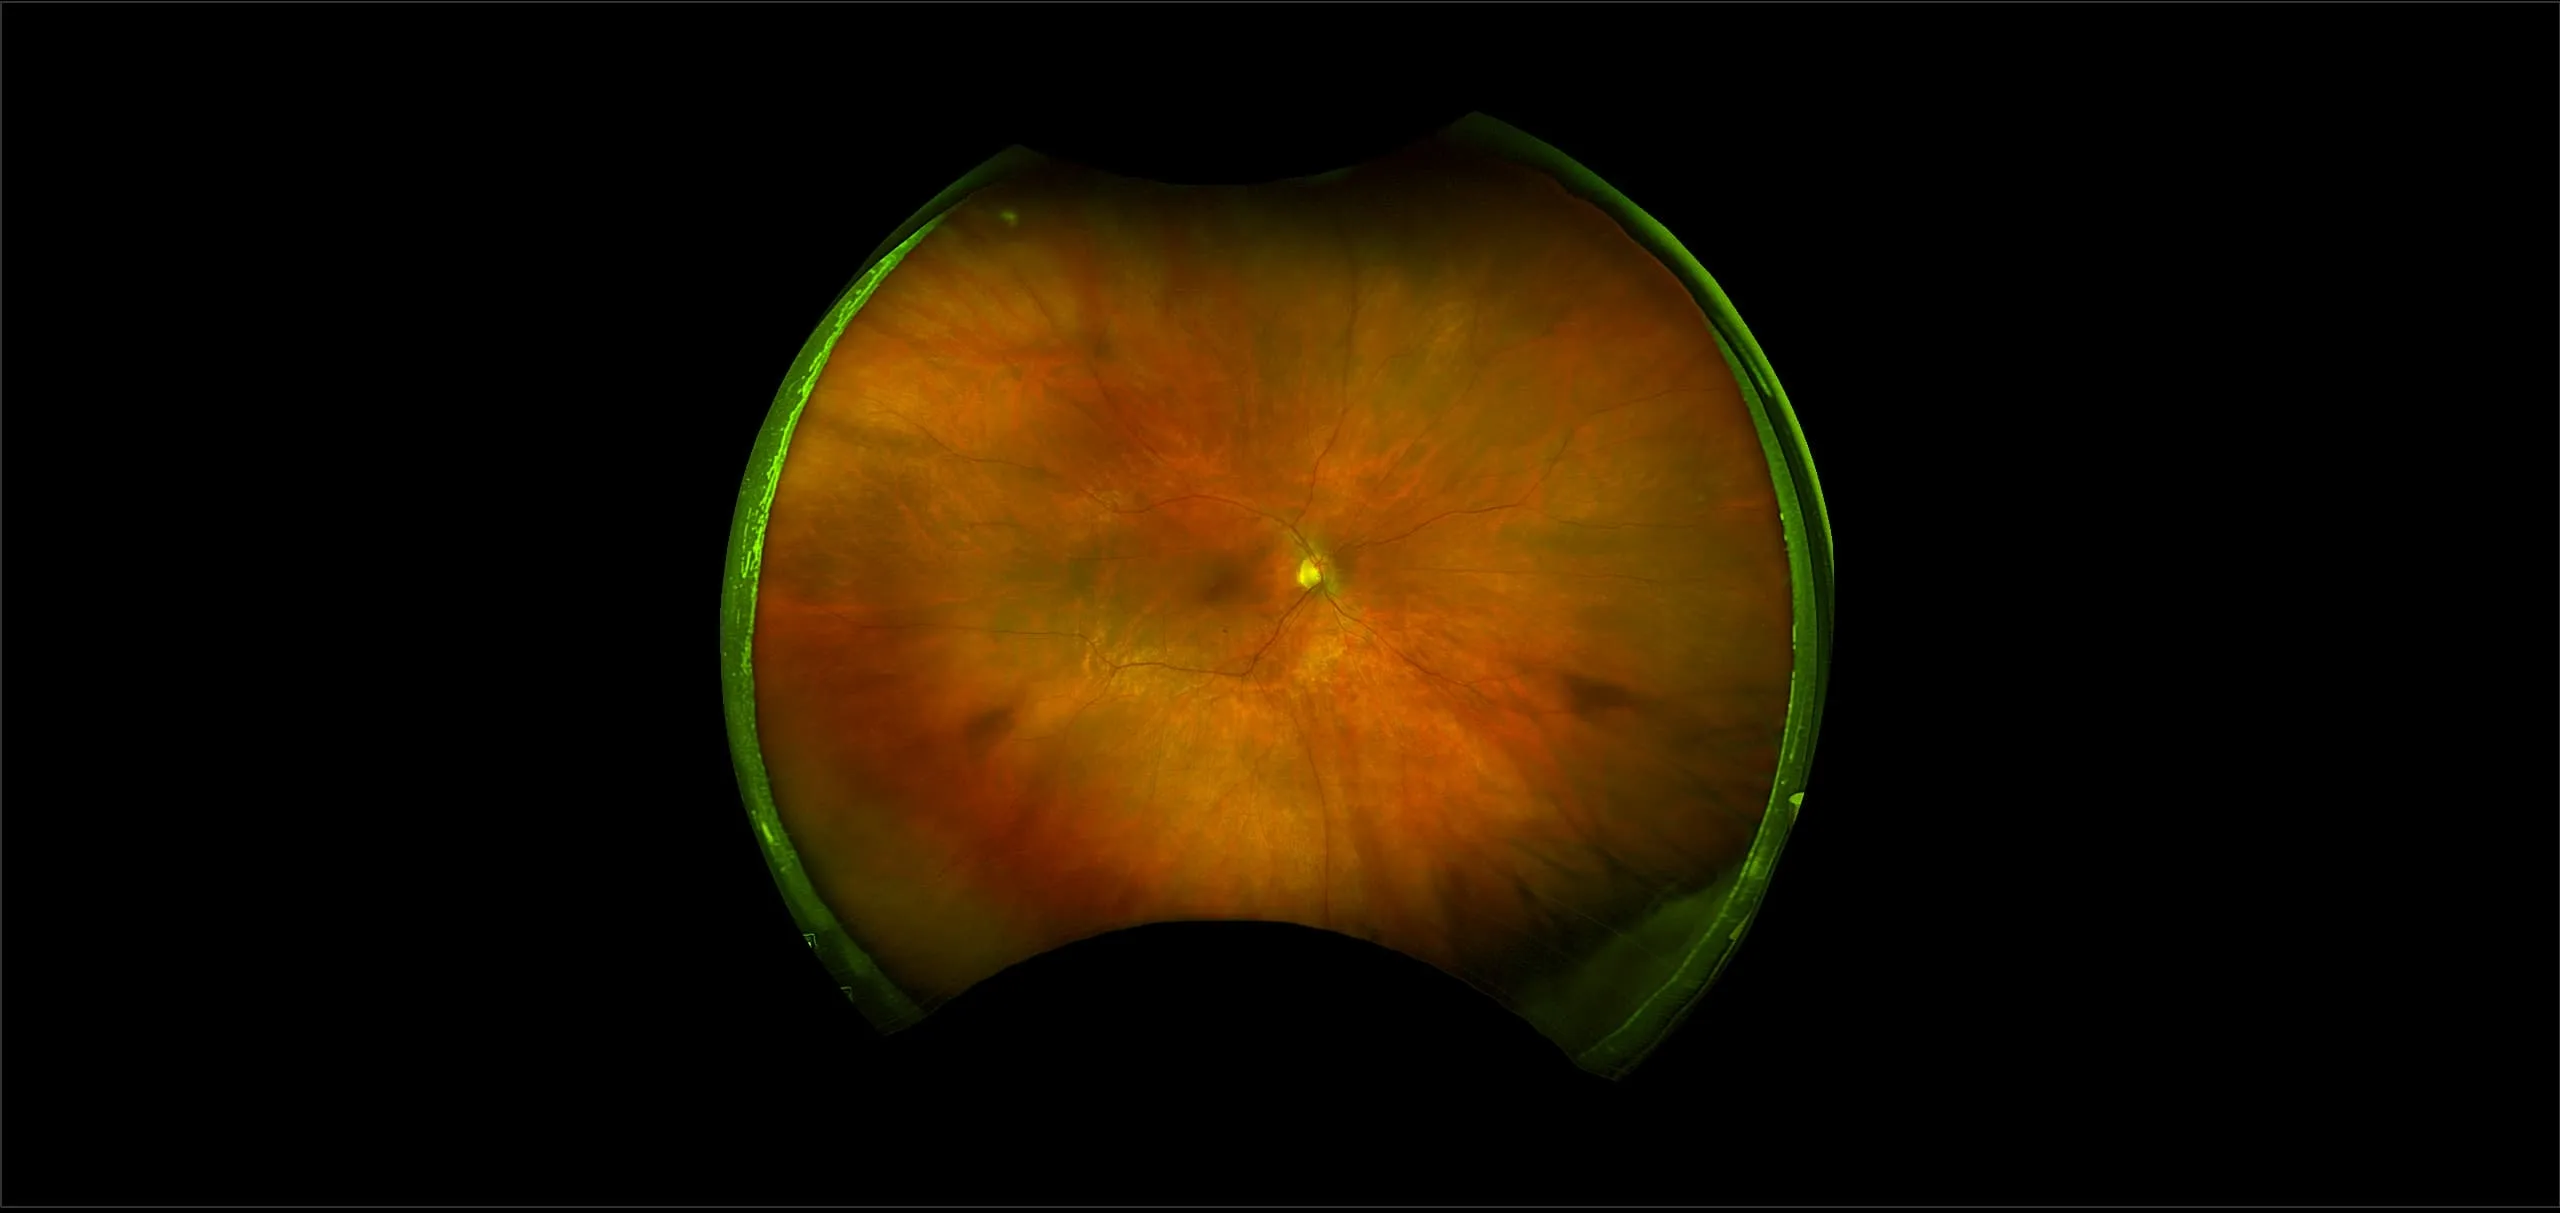

MonacoPro - Retinal Detachment, RG, AF, OCT

A retinal detachment (RD) is the separation of the sensory retina from the Retinal Pigment Epithelium (RPE) (outer segments of the photoreceptors from the microvilli of the RPE).